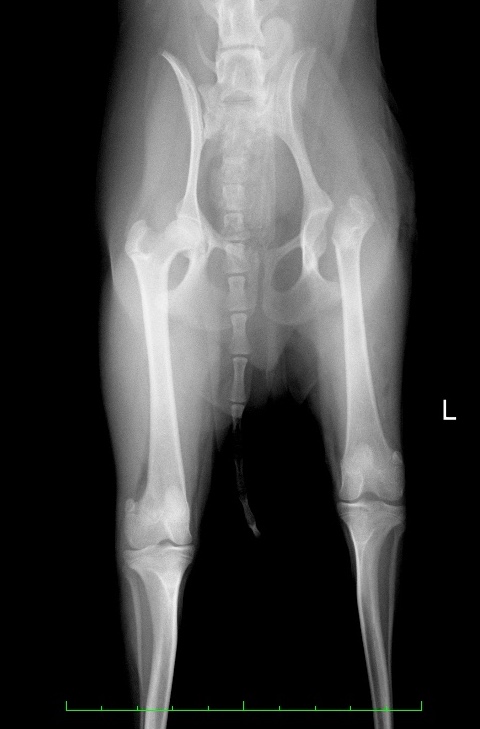

術前の股関節のX線写真では、正常な右の大腿骨頭は綺麗な球形ですが、左は球形が崩れ、X線の透過性も変化しまだらに見えています。(赤矢印)

またモモの筋肉の太さが明らかに違います。(緑線)

罹患肢の左が細いのは、廃用性萎縮といい、痛みによって長期間うまく体重をかけられなかった結果として筋肉が痩せてしまったことによります。

術前X線